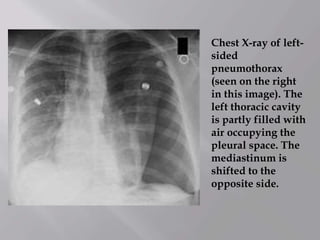

Chest X-ray of left-

sided

pneumothorax

(seen on the right

in this image). The

left thoracic cavity

is partly filled with

air occupying the

pleural space. The

mediastinum is

shifted to the

opposite side.